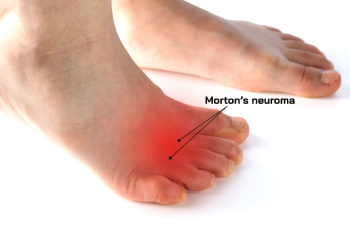

Bunions, plantar fasciitis, and Morton’s neuroma are common foot disorders that cause pain and difficulty walking. A bunion occurs when the big toe deviates from the smaller toes, creating a bony bump at the base of the joint. A podiatrist can recommend modifying footwear, using orthotic devices, or, in persistent cases, performing surgery to correct the deformity. Plantar fasciitis, a painful inflammation of the connective tissue along the bottom of the foot, often causes heel pain, especially after periods of rest. Treatment includes stretching, wearing supportive footwear, orthotic inserts, or surgery, if symptoms remain after more conservative care. Morton’s neuroma involves thickening of nerve tissue between the toes, often leading to burning pain or numbness in the ball of the foot. A podiatrist may suggest shoe modifications, metatarsal pads, or carefully considered injections. If necessary, surgery may be needed to remove the affected nerve. If you regularly experience foot pain, it is suggested that you schedule an appointment with a podiatrist for a diagnosis and appropriate treatment.

Morton’s Neuroma Facts

Morton's neuroma is a painful condition involving the thickening of tissue surrounding one of the nerves leading to the toes, most commonly between the third and fourth toes. This irritation causes nerve compression, often resulting in a sharp, burning pain in the ball of the foot, as well as numbness or tingling in the toes. The condition can be triggered by repetitive stress, improper footwear, or foot deformities like flat feet or high arches. Wearing tight shoes or high heels can place added pressure on the forefoot, increasing the risk of developing this condition. Athletes who engage in high-impact sports may also be more vulnerable. If you have pain in this part of your foot, it is suggested that you promptly contact a podiatrist who can provide an accurate diagnosis and treatment.

Morton’s Neuroma

Morton's neuroma is a painful foot condition that commonly affects the areas between the second and third or third and fourth toe, although other areas of the foot are also susceptible. Morton’s neuroma is caused by an inflamed nerve in the foot that is being squeezed and aggravated by surrounding bones.

What Increases the Chances of Having Morton’s Neuroma?

- Ill-fitting high heels or shoes that add pressure to the toe or foot

- Jogging, running or any sport that involves constant impact to the foot

- Flat feet, bunions, and any other foot deformities

Morton’s neuroma is a very treatable condition. Orthotics and shoe inserts can often be used to alleviate the pain on the forefront of the feet. In more severe cases, corticosteroids can also be prescribed. In order to figure out the best treatment for your neuroma, it’s recommended to seek the care of a podiatrist who can diagnose your condition and provide different treatment options.